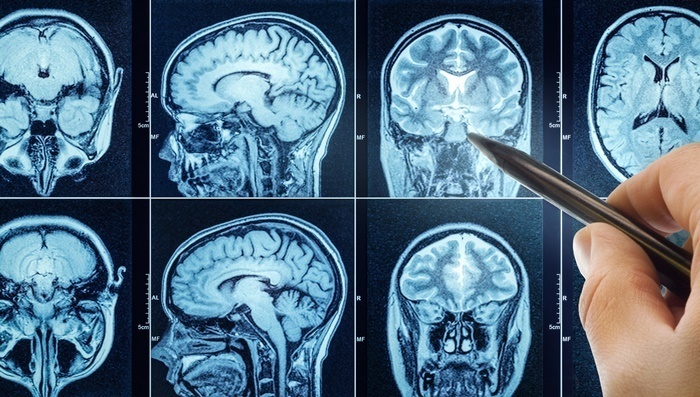

실제로 뇌종양은 증상이 없거나 매우 모호하게 나타나기 때문에 조기에 발견하기 어렵다. 뇌종양은 뇌 속에 생긴 비정상적인 세포 덩어리로, 양성과 악성으로 나뉜다.

양성 종양은 비교적 성장 속도가 느리고 다른 조직으로 퍼지지 않지만, 위치에 따라 신경을 압박해 다양한 증상을 유발할 수 있다. 반면 악성 종양은 빠르게 자라고 전이 가능성이 있으며, 생명에도 영향을 줄 수 있다.

뇌종양의 증상으로는 두통, 구토, 시야 장애, 기억력 저하, 성격 변화, 발작 등이 있으며, 초기에는 일반적인 피로나 스트레스로 오인될 수 있어 주기적인 검진이 중요하다.

뇌종양은 누구에게나 발생할 수 있는 질환이지만, 증상이 뚜렷하지 않고 초기 발견이 어려워 종종 치료 시기를 놓치게 된다. 김지석처럼 건강검진을 통해 조기에 발견하는 경우, 예후가 좋고 치료 부담도 낮다. 전문가들은 특히 40대 이후부터는 2~3년에 한 번씩 뇌 MRI를 포함한 종합 건강검진을 받을 것을 권장한다.